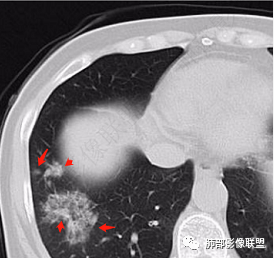

2、CT表现为两肺下叶结节影、斑片影、磨玻璃影,沿支气管血管束分布,部分支气管壁显示增厚。粗略一看部分病灶内似可见“细网格影”,但是仔细观察,可发现此“细网格影”不同于我们常见的“细网格影”,尤其是右肺下叶病灶,可以观察到病灶内部的网格上有高密度结节感或颗粒感,部分层面见“反晕征”,且反晕的边缘亦可观察到结节感。未见胸腔积液。

3、反晕征又称为环礁征、环岛征或环状珊瑚岛征,表现为中心磨玻璃影,周围为高密度影环绕,最初被认为是隐源性机化性肺炎(COP)的特征性表现之一,但随后不断有研究发现反晕征亦可出现在多种感染及非感染性疾病、肿瘤及非肿瘤性疾病中。反晕征的常见疾病谱有:①感染性疾病:肺孢子菌病、侵袭性肺真菌感染、肺结核、病毒性肺炎;②非感染性疾病:肺淋巴瘤样肉芽肿、韦格氏肉芽肿、 结节病、机化性肺炎(包括隐源性和继发性)、肺栓塞;③肺腺癌以及肺肿瘤治疗后。

2、好发部位与其它结核类似,上叶及下叶背段为主。 3、烟花征,反晕征,环呈结节状,可以伴随空洞,树芽征,结节灶,胸水。(反晕征:一般周围实性环形高密度影,中央呈低密度;一般环超过圆的3/4,结核的环主要是小叶核心结节组成,类似于多发树芽征聚集,边缘结节感。中央的晕:可以是腺泡结节,树芽征,细网状,磨玻璃影,很少正常,主要成分是小叶内间质增厚、小叶核心结节、肺泡内病变。)其实也体现了结核的多灶性、多态性特点。

4、其实不一定完全表现为反晕征,还有比较密集的烟花,聚集成团,与反晕征同在。